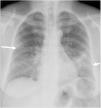

Se encontró un patrón alveolar en el 22,3% de las radiografías iniciales (fig. 4), opacidades lineales (fundamentalmente atelectasias laminares) en el 47,2% y ambos hallazgos en el 9,8% de los casos. La concordancia interobservador con respecto a las opacidades lineales correspondió a kappa=0,798 y 90,3% de correlación. En cuanto a la afectación alveolar, resultó ser de kappa=0,943 y 98,86% de correlación (tabla 1).

Mujer de 55 años con infección por COVID-19. La radiografía posteroanterior de tórax muestra una opacidad focal periférica en campo medio derecho (flecha), una consolidación focal en campo medio/base izquierda y una opacidad lineal en la base izquierda (fleche corta). Cuantificación: 4/6 campos y 5/8 campos, que corresponden a afectación grave en sistema 6A, moderada en sistema 6B y moderada en sistema 8.